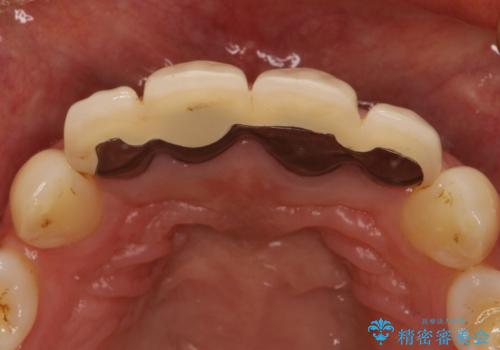

以前に装着されていたものは全て連結されており、清掃性があまり良くありませんでした。

一つ一つを独立したかぶせ物を装着することで、フロスも可能になり、清掃性が向上しました。